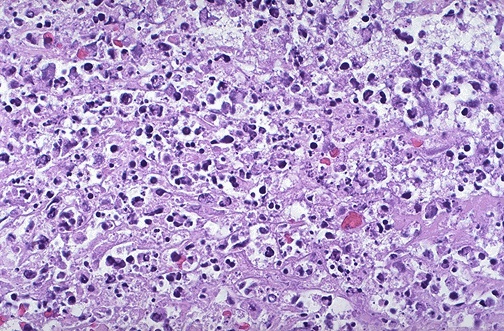

| When there is marked cellular injury, there is cell death. This microscopic appearance of myocardium is a mess because so many cells have died that the tissue is not recognizable. Many nuclei have become pyknotic (shrunken and dark) and have then undergone karorrhexis (fragmentation) and karyolysis (dissolution). The cytoplasm and cell borders are not recognizable. |